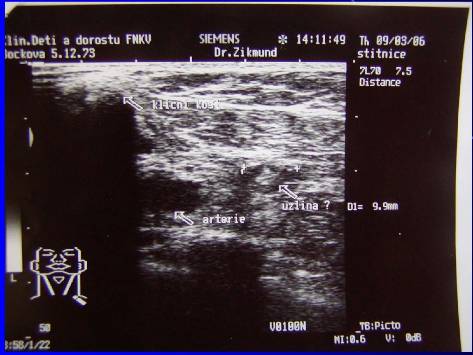

1.Recidiva Ca mammae (pac. L.B.. tumor. markery, UZ, CT, CT-PET, exstirpace susp. uzliny-biopsie)

Recidiva Ca mammae (pac.L.B. tumor. markery, UZ, CT, CT-PET, exstirpace susp.uzliny-biopsie)

Recidiva Ca mammae (pac.L.B.. tumor. markery, UZ, CT, CT-PET, exstirpace susp.uzliny-biopsie)

Recidiva Ca mammae (pac. L.B. tumor. markery, UZ, CT, CT-PET, exstirpace susp.uzliny-biopsie)